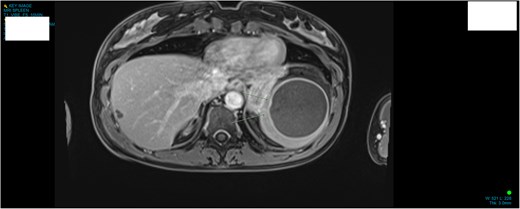

A 34-year-old woman presented to the Emergency Department with upper abdominal pain of a few days’ duration with associated nausea. She had no past medical or surgical history. She was hemodynamically stable. Routine blood work and beta human chorionic gonadotrophin were normal. Initial investigation included a Pelvic Ultrasound Scan which showed a complex cystic lesion on the superior aspect of the spleen measuring 64 × 62 × 62 mm. Further investigation with serial imaging including Commuted Tomography (CT), Magnetic Resonated Imaging (MRI) and Proton Emission Topography (PET) demonstrated a cystic lesion of the upper pole of the spleen with an enhancing mural nodule and radiological appearance of a dermoid cyst (Figs 1 and 2). This nodule was found to have low grade avidity on PET scan. The splenic vasculature demonstrated a magistral arrangement on contrast enhanced CT. Hydatid Serology was negative.

MRI demonstrating anatomical location and size of lesion sagittal plane.